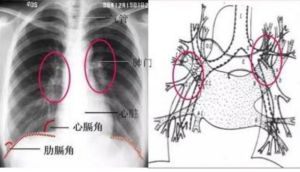

胸腹部的矛盾呼吸是指呼吸時胸廓與腹部出現相反運動,該表現是呼吸肌疲勞的可靠臨床徵象,也是給予人工通氣的適應症。另外,重症哮喘也可出現矛盾呼吸。

矛盾呼吸又叫反常呼吸,是指相鄰的多根肋骨多處骨折時,可造成胸壁浮動。吸氣時浮動的胸壁塌陷,呼氣時則向外隆起。這種現象恰與正常呼吸運動相反,稱之為矛盾呼吸。